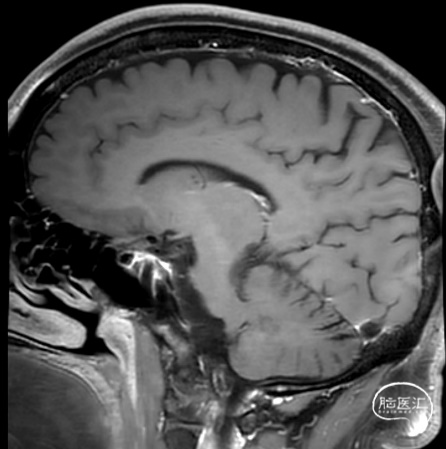

男性,38岁。

主诉:突发头痛、头晕1天。

既往史:无特殊。

查体:GCS 评分14分。

1. 蛛网膜下腔出血

2. 左侧大脑中动脉分叉部动脉瘤